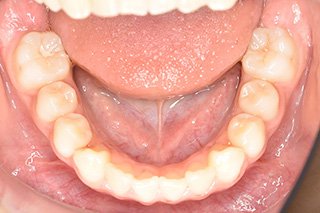

顎顔面矯正症例 11歳女児 Case

| 主訴 | 永久歯が変な所からはえてきている|顔貌 | |

|---|---|---|

| 施術内容 | 矯正1期治療 | |

| 治癒期間 | 1年5ヶ月間 | |

| 費用 | 459,200円(税込) | |

| リスク・ 副作用 | 痛みを伴う | |